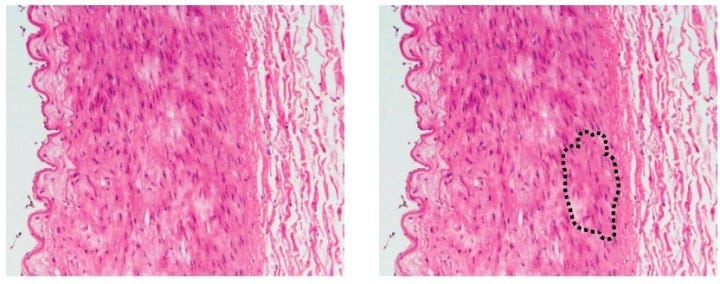

The first of these algorithms is one of the multiple existing examples of an algorithm called DLAD (Deep Learning based Automatic Detection) to analyze chest radiographs and detect abnormal cell growth, such as potential cancers. The algorithm’s performance was compared to multiple physician’s detection abilities on the same images and outperformed 17 of 18 doctors. The second of these algorithms, LYNA (Lymph Node Assistant), to identify metastatic breast cancer tumors from lymph node biopsies. This isn’t the first application of AI to attempt histology analysis, but interestingly this algorithm could identify suspicious regions undistinguishable to the human eye in the biopsy samples given. LYNA was tested on two datasets and was shown to accurately classify a sample as cancerous or noncancerous correctly 99% of the time.

这些算法中的第一个是称为DLAD (基于深度学习的自动检测)算法的多个现有示例之一,该算法可分析胸部X射线照片并检测异常细胞生长,例如潜在的癌症。 将算法的性能与同一图像上多个医师的检测能力进行了比较,其性能优于18位医生中的17位。 这些算法中的第二种算法是LYNA (淋巴结辅助),可从淋巴结活检中识别出转移性乳腺癌肿瘤。 这不是AI尝试进行组织学分析的第一个应用程序,但有趣的是,该算法可以在给定的活检样本中识别人眼无法区分的可疑区域。 LYNA已在两个数据集上进行了测试,结果显示99%的时间正确地将样品正确分类为癌性或非癌性。

The left panel shows the image fed into an algorithm. The right panel shows a region of potentially dangerous cells, as identified by an algorithm, that a physician should look at more closely. Both LYNA and DLAD serve as prime examples of algorithms that complement physicians’ classifications of healthy and diseased samples by showing doctors salient features of images(Greenfield, n.d.).

左面板显示了输入算法的图像。 右面板显示了由算法识别的潜在危险细胞区域,医生应仔细观察。 LYNA和DLAD都是算法的主要示例,通过显示医生的图像显着特征来补充医生对健康和患病样品的分类(Greenfield,nd)。